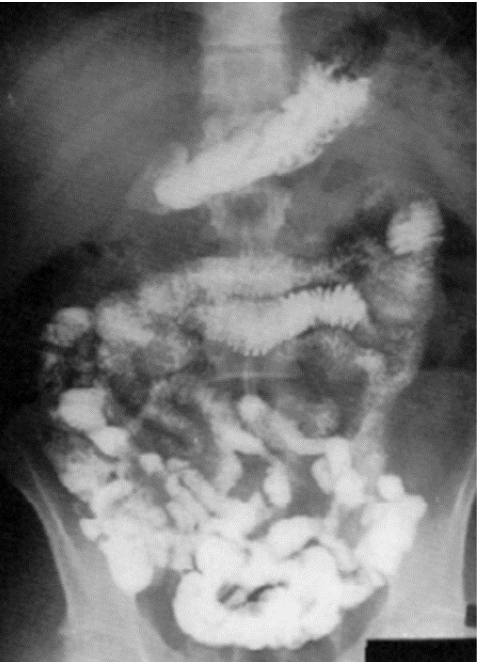

What contrast procedure was performed to produce this image?

Small Bowel Follow-Through (SBFT)

1)Small Bowel Follow-Through (SBFT)

2)Barium Sulfate

3)how quickly and efficiently the small intestine moves

4)observe motality